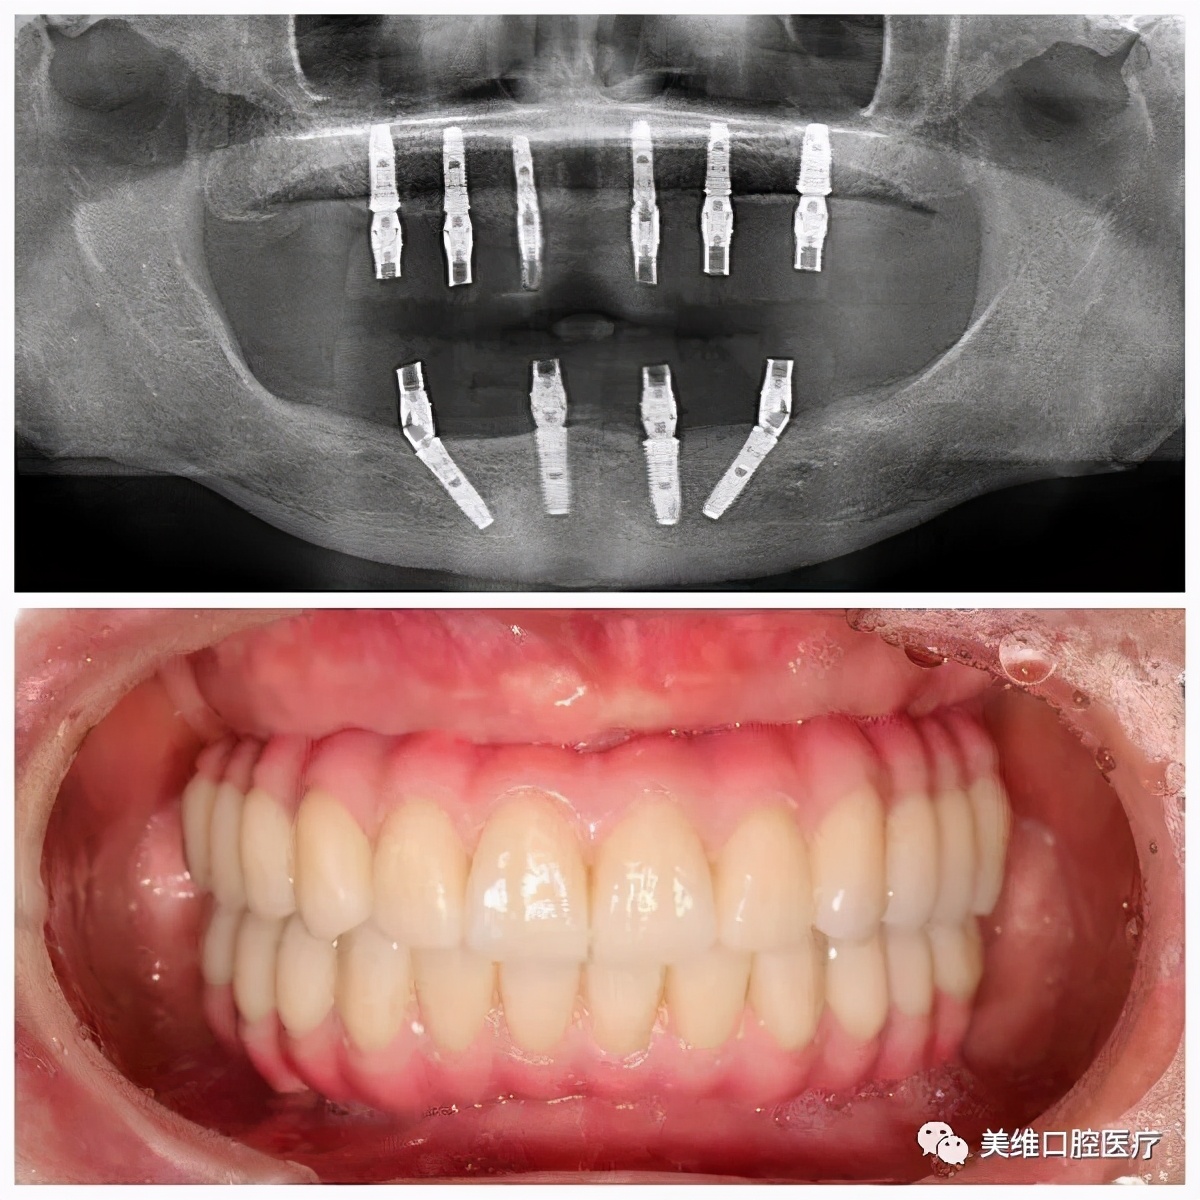

尽管得益于健康生活习惯,郑老心肺功能、血检报告都很好,但因为常年佩戴假牙使原本的好牙都已松动,而且牙槽骨有一定萎缩,王建文考虑到郑老身体健康状况允许,且急切想改善生活质量,因此为她量身定制了全口即刻种植方案。因为种植牙的咀嚼方式与真牙完全一样,异物感小,不论从美观层面,还是咀嚼效率层面,都比传统假牙有大幅度提高。

经过术前周密的种植方案设计,并通过 3D 打印技术制作出精密的种植手术导板,期盼已久的郑老终于迎来了数字化微创种植手术,短短三小时就让郑老师长出了一口「新牙」,不仅免去了多次奔波的辛劳,而且创口小,大大降低了患者的术后疼痛感和恐惧感,看着自己因「新牙」而越发显得年轻了,郑老露出了舒心而满意的笑容。

他埋头研究最新修复技术,逐项攻克了前牙美学种植、即刻拔牙种植、现代微创种植……每一个阶段都取得了不小的成就,对上颌窦内、外提升术、骨移植术、各类复杂的半口全口种植手术、All-on-4、All-on-6 即刻种植修复等疑难种植手术有着丰富的经验,并以擅长前牙个性化全瓷美容修复而著称,成为了不折不扣的「种植修复狂人」!